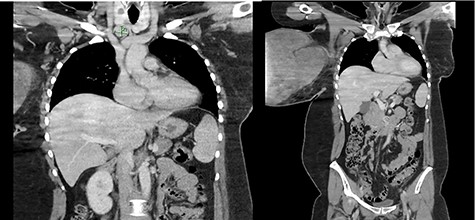

The patient was non-compliant and attempted to abscond as soon as the infection improved with intravenous Flucloxacillin, despite explanation of its risks. In light of the patient’s non-compliant behaviour and risk of being lost to follow-up, preoperative biopsy of lymph nodes was thus abandoned, and the decision was made for a semi-urgent surgery. Informed consent was obtained, and the patient underwent a right mastectomy and axillary clearance. Elliptical incision was made while preserving surrounding healthy tissue. The excised mass was 310 × 200 × 240 mm in size (Fig. 3). Level I and II axillary clearance was performed. Due to laxity of the skin, primary closure was achieved.

Histology of the excised mass demonstrated mitotic count of 7 out of 10 high-power field (HPF) with stromal overgrowth confirming the diagnosis of borderline PT with negative margins. A total of 25 lymph nodes were harvested, and all demonstrated reactive follicular hyperplasia.